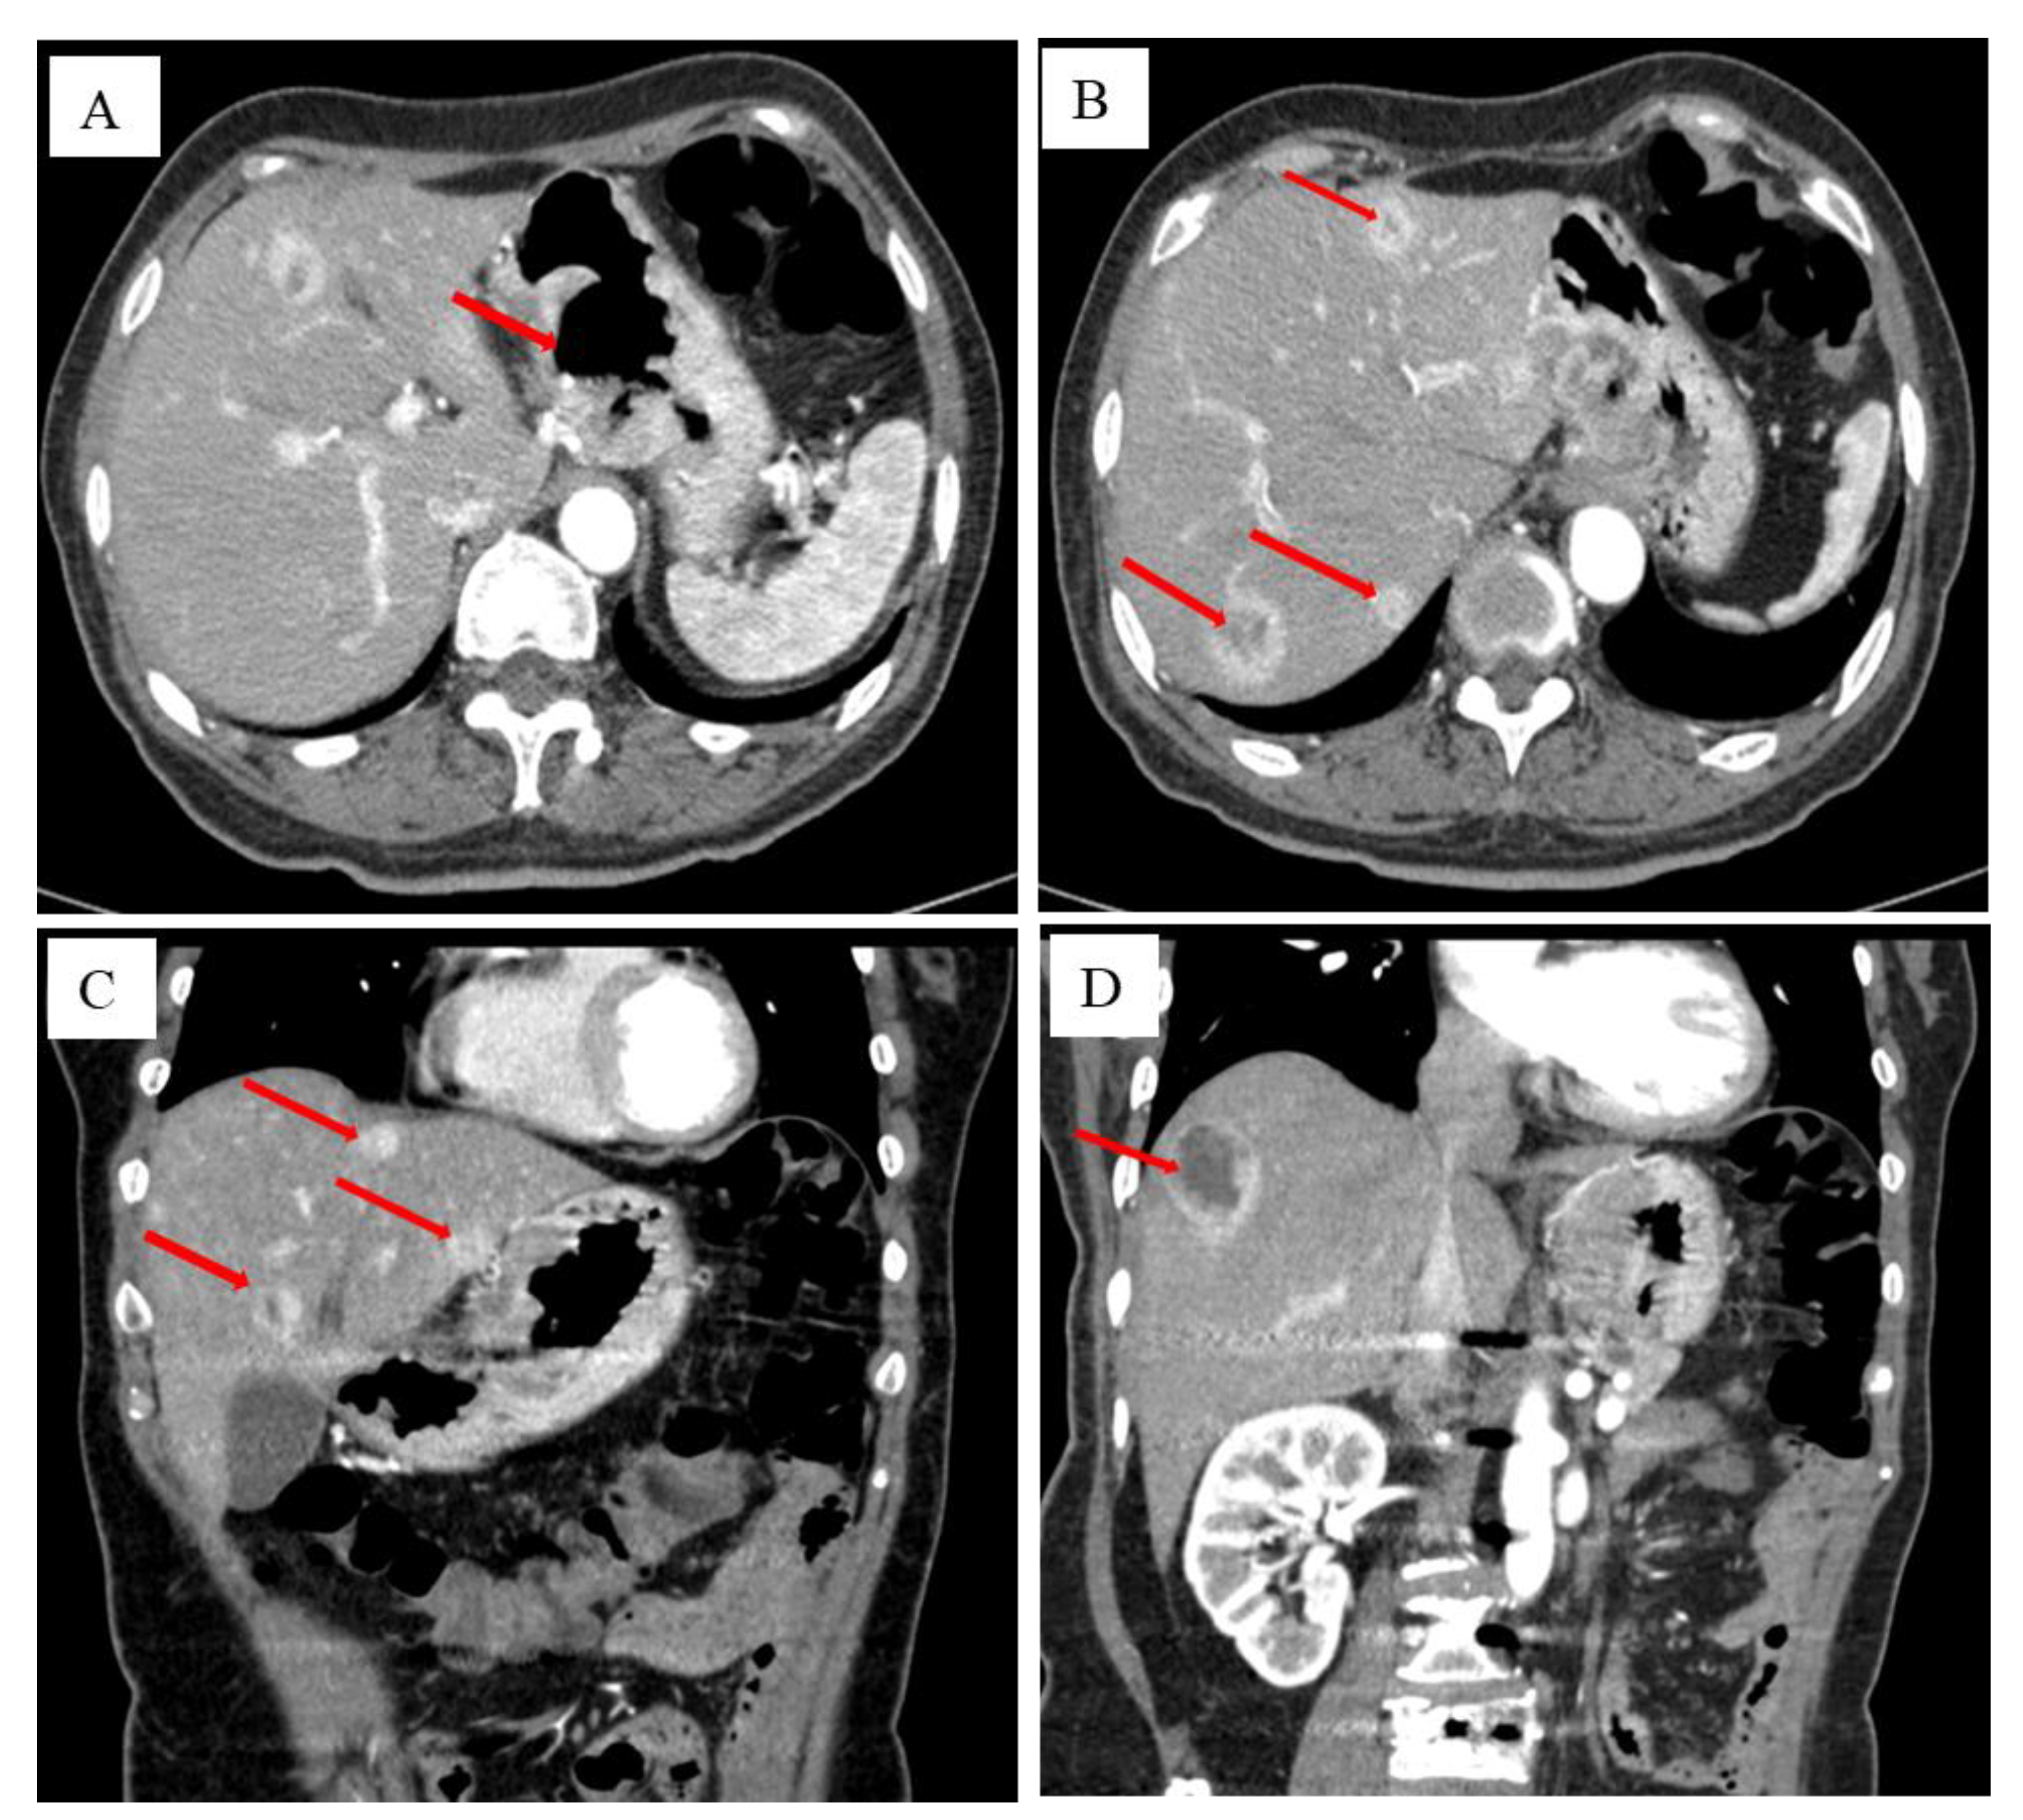

A 76-year-old female patient had intermittent abdominal pain and discomfort two years ago. It was located under the sword process, showing a hidden pain, and it was sustainable. Pain after eating a meal was significantly reduced. The patient came to our hospital for a gastroscopy. The results of the gastroscopy are shown in Figure 1, which suggest gastric stomach cancer. After the patient was admitted to the hospital, the upper abdomen was imaged using a contrast-enhanced computed tomography (CT) (Figure 2).

Figure 2.

The patient’s results from the CT examination after admission. After the patient was admitted to the hospital, the transverse section of the upper abdomen was imaged using a contrast-enhanced CT, showing gastrointestinal lesions, which are like a volcanic mouth (red arrow) (A). The transverse section indicates gastric cancer metastases to the liver (red arrow) (B). The median sagittal section shows that gastric cancer is accompanied by liver metastasis (red arrow) (C). The coronal section shows that gastric cancer is accompanied by liver metastasis (red arrow) (D). The patient is diagnosed with malignant tumours of the gastric gastrointestinal side and ulcers, lymphatic metastasis to the liver and gastrointestinal ligament area, and multiple metastases in the liver. QIAN XH et al. find that GIST is generally considered to originate from the Khalk cell ICC. Most of the GIST occurs in the stomach, followed by small intestines, the colon, and the oesophagus [6]. Malignant GISTs can be transferred to the liver through blood circulation, and those that occur in the liver are basically the gold standard for transferring liver GISTs.